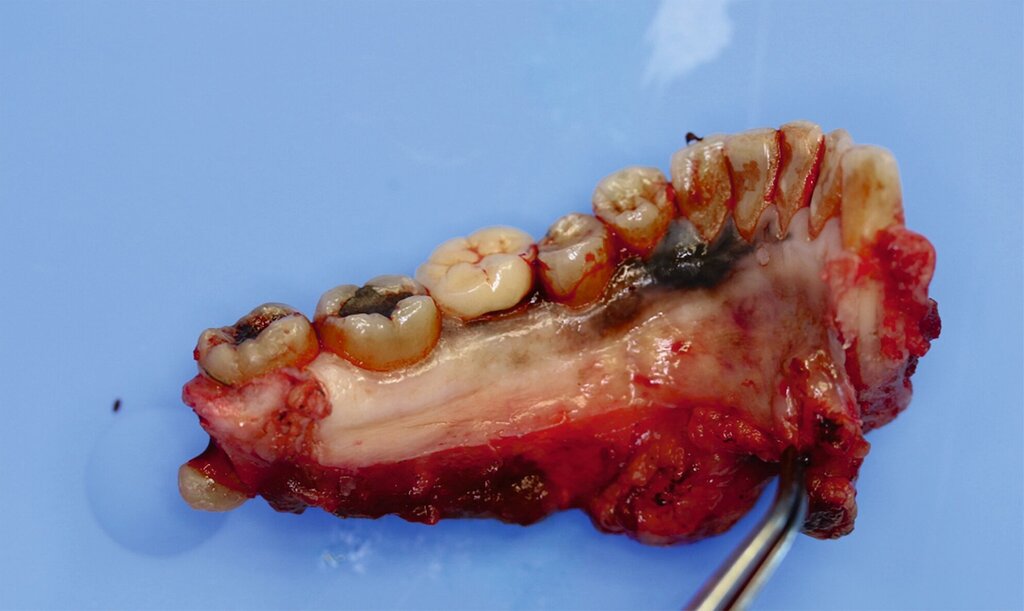

Eine im Januar 2024 alio loco durchgeführte Probenentnahme ergab eine resorptive Entzündung mit Pigmenteinlagerungen. Die Patientin berichtet, dass die Schleimhautveränderung etwa vier Wochen vor der Vorstellung bei uns begonnen habe zu wuchern. Klinisch zeigte sich eine 10 mm x 7 mm messende, exophytisch wachsende, schwarz pigmentierte Raumforderung (Abbildungen 1 und 2). Durch eine Probenentnahme in domo konnte histopathologisch ein malignes Melanom gesichert werden.

Die prätherapeutische Fallvorstellung im interdisziplinären Hauttumorboard ergab die Empfehlung zur primären Resektion und zu einer Halslymphknotenentfernung der Level I–III beidseits. Diese erfolgte im Sinne einer kontinuitätserhaltenden Unterkieferteilresektion (Abbildungen 4 bis 6). Die Rekonstruktion erfolgte durch ein mikrochirurgisch anastomosiertes, fasziokutanes Radialistransplantat vom linken Unterarm. Der Entnahmedefekt wurde mittels Vollhaut vom linken Unterarm gedeckt. Zudem wurde eine beidseitige selektive Halslymphknotenausräumung in Level IA, IB, IIA, IIB und III durchgeführt. Die Patientin konnte in gutem Allgemeinzustand am 15. postoperativen Tag entlassen werden.